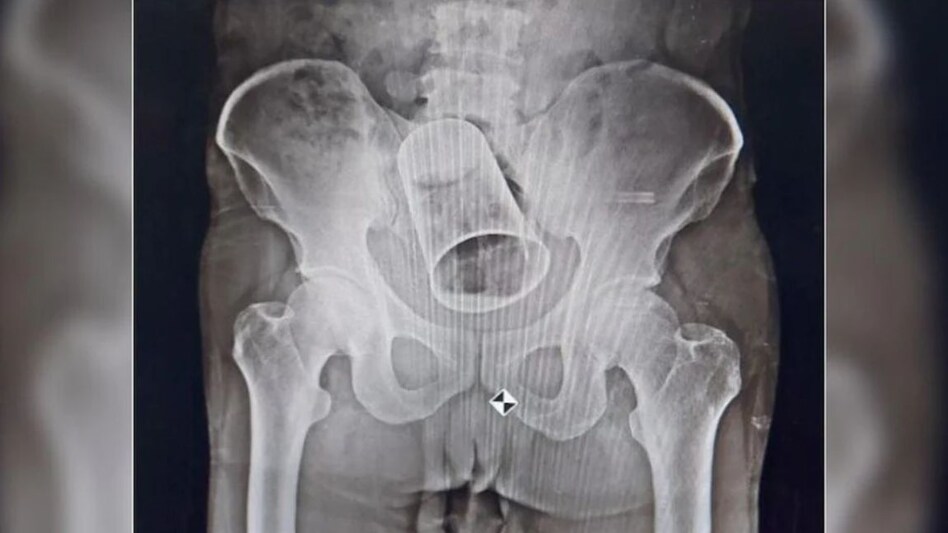

Odisha Crime News: ओडिशा के ब्रह्मपुर (Brahmapur, Odisha) में डॉक्टरों (Doctor) ने एक्सरे रिपोर्ट में कुछ ऐसा दिखाया, जिसे जानकर हर कोई हैरान है. दरअसल, यहां डॉक्टरों ने ऑपरेशन करके शख्स की आंत से स्टील गिलास को बाहर निकला. मामला ब्रह्मपुर के एमकेसीजी मेडिकल कॉलेज का है. बताया जा रहा है, शख्स को उसके दोस्त ने शराब पिलाकर प्राइवेट पार्ट के रास्ते गिलास डाल दिया था.

जैसे ही वह अपने घर पहुंचा तो देखा कि उसके पेट में सूजन आ गई थी. परिवार वालों को कृष्णा ने फिर सारी बात बताई और एमकेसीजी अस्पताल में चेकअप करवाया. कृष्णा की जब X-Ray रिपोर्ट आई तो पता चला उसकी आंत में स्टील का गिलास फंस गया है. डॉक्टरों ने पहले मलाशय के माध्यम से कांच निकालने की कोशिश की. लेकिन आंत के बीच गिलास इस तरह फंसा हुआ था कि उसे निकाला नहीं जा सका.